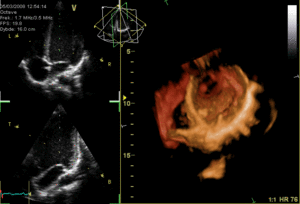

يتم تخطيط صدى القلب عبر المريء عن طريق مسبار يتم إدخاله عن طريق الفم إلى المريء، وذلك للحصول على "نافذة" أفضل موجات فوق صوتية|للموجات فوق الصوتية]] لرؤية الأقسام الخلفية من القلب، إذ أن هذه الجوانب تكون بعيدة عن الصدر، فتكون الصور التي يتم الحصول عليها من الصدر غير واضحة، بينما حينما يتم الفحص من المريء - الذي يُجاور القلب من الخلف مباشرة - أدق للأقسام الخلفية، كما يمكن إنتاج صور ثلاثية الأبعاد[5] لصمامات القلب.

صورة ثلاثية الأبعاد للصمام التاجي. |